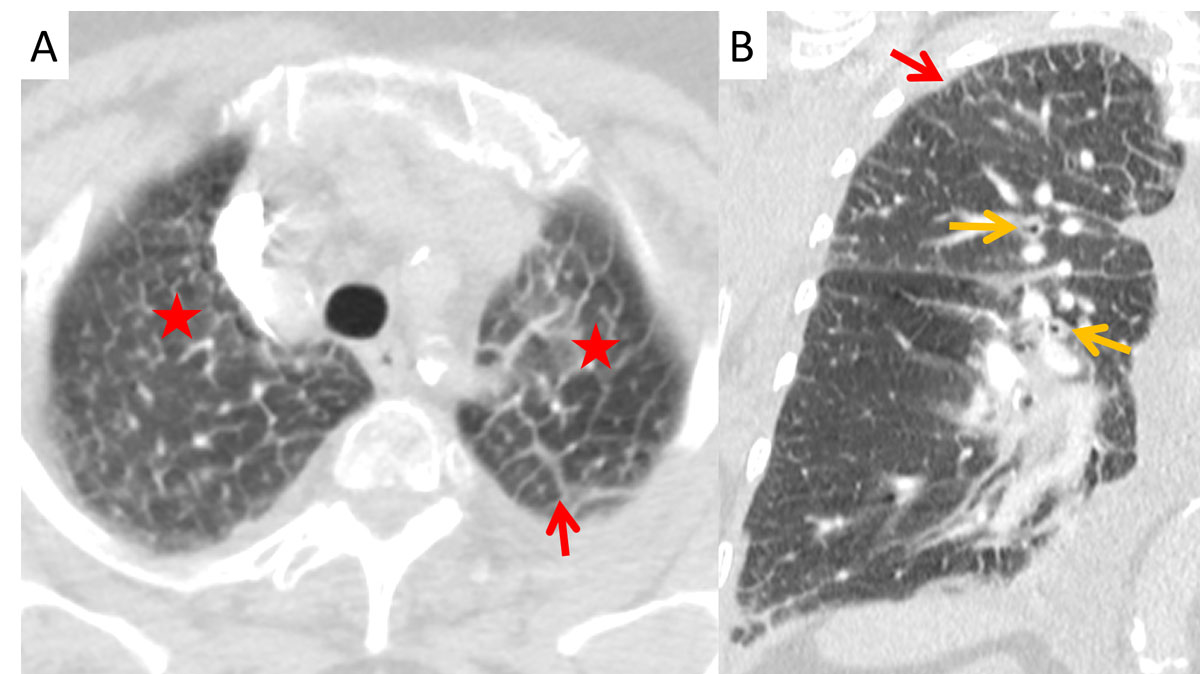

The cardiothoracic ratio and the diameters of the superior and inferior vena cava were measured. Pleural effusion, peribronchial cuffing, interlobular septal thickening (Kerley B lines, see figs 1 and 2 ), ground glass opacity and consolidation were analysed for prevalence, distribution and quantity. To determine the cardiothoracic ratio, the maximum horizontal diameter of the heart in the axial plane and the maximum inner thoracic diameter (inner edge of ribs / edge of pleura) were captured and divided. The diameters of the superior and inferior vena cava (short axis) were measured on an axial plane just before their entrance into the right atrium of the heart. Thickening of the interlobular septa and the bronchial walls (peribronchial cuffing) was graded as 1 if <1 mm, 2 if 1–3 mm or 3 if >3 mm. The amount of pleural effusion was visually estimated as low grade (trace of effusion), moderate (<500 ml) and high-grade (>500 ml). The amounts of ground glass opacity and consolidation were graded from 1 to 3 (+, ++, +++) in each region. The distributions of these latter patterns were analysed in four anatomical regions separately (z-axis): apex (uppermost 2 cm of the lungs), upper lungs (cranial of the aortic arch), middle lungs (cranial of the lower lung veins) and lower lungs (heart level and lower). In addition, the oedema patterns were classified into predominantly central with subpleural spearing (butterfly oedema) and gravity oedema (lower dorsal parts of the lungs most affected).

Interlobular septal thickening (IST) in the lung apex was present in of 81% and 76% of the cardiac and renal groups, respectively, which was significantly more than in the ILD group (26%, p <0.0001, figs 1–4 ). The distribution in the insufficiency group was more homogenous throughout the lungs than in the ILD group, in which the amount of septal thickening increased to 90% towards the lower lobes (table 2). The average thickness of the interlobular septa was rated between 1 and 2 with significantly thicker septal lines in the insufficiency group (1.45 ± 0.6) compared with the ILD group (1.28 ± 0.5; p <0.0001, fig. 3).

Figure 4 Apical Kerley B lines (red arrows) in (A) axial and (B) coronal planes with peribronchial cuffing (orange arrows) and ground glass opacities (asterisk) from transudation in a 63-year-old male patient with renal insufficiency.

Peribronchial cuffing was significantly more often present in the cardiac than in the renal and ILD groups, in 67%, 29% and 12% of patients, respectively (p = 0.04 and p <0.0001). The average thickness of the bronchi did not differ significantly between the various groups, ranging from 1.27 to 1.4 (SD 0.5–0.8) with p-values >0.9 (fig. 4).

In this study, more than 80% of the patients with cardiac insufficiency and more than 70% of the patients with renal insufficiency presented with IST (Kerley B lines) in the lung apex. Miniati et al. described an identical distribution of the septal lines on conventional chest x-ray in the lower lungs among patients with heart or renal insufficiency [19]. While their distribution in the insufficiency group was homogenously throughout the lungs, the amount of Kerley B lines in our study increased to 90% towards the lower lobes in the ILD group. Findings of ILD predominate in the lung bases [8]. Patients with heart or renal insufficiency showed peribronchial cuffing due to increased capillary hydrostatic pressure or decreased oncotic pressure [1, 20]. One reason for the apical prevalence of the Kerley B lines in congested patients could be the redistribution of the pulmonary blood flow into the cranial parts of the lung, probably increasing the capillary pressure with resultant transudation. Kerley B lines are not a new sign in chest radiology, but their location in the lung apex is here described for the first time.

In our cohort the best sign for differentiating pulmonary congestion seemed to be peribronchial cuffing, which was twice as prevalent with cardiac insufficiency as with renal insufficiency (p = 0.04). In CT imaging, pulmonary congestion can best be differentiated from ILD using the diameter of the vena cava, the presence of pleural effusion, peribronchial cuffing and apical Kerley B lines (each p <0.0001).